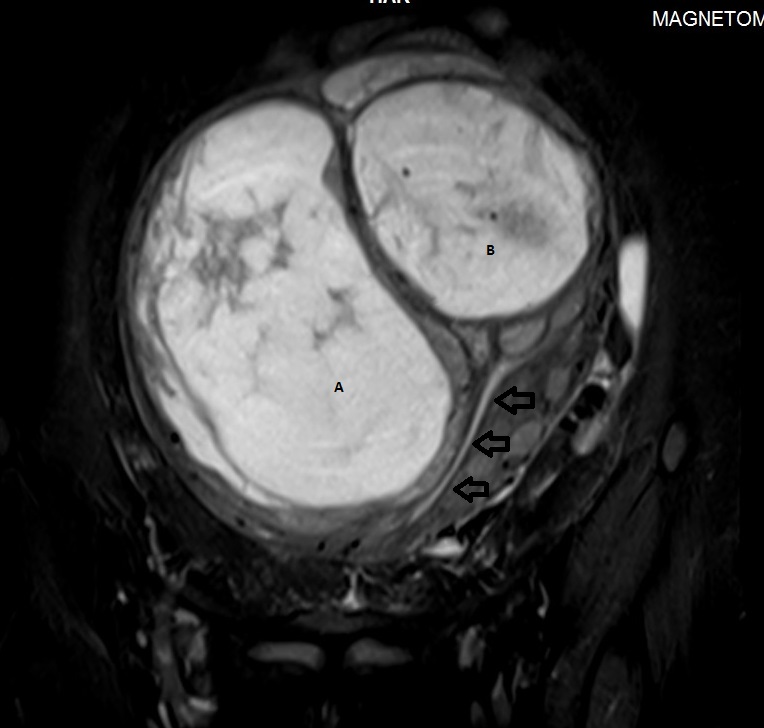

MRI pelvis of a large posterior wall fibroid with cystic degeneration …

MR imaging of atypical fibroids

Pelvic MRI for Fibroids – Why You Need an MRI to Detect Fibroids

Huge intramural fibroid | Image | Radiopaedia.org

Additional pathologies found during uterine fibroid MRI screening. a …

Huge intramural fibroid | Image | Radiopaedia.org

Fibroids UFE | Body MRI